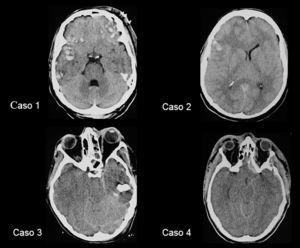

A pesar del tratamiento correctamente secuenciado las PIC permanecieron elevadas en los 4 casos. Basándonos en los criterios de Münch, aunque no permitimos que la cifra de PIC llegara a 25 mmHg, y debido a los graves efectos secundarios metabólicos y hemodinámicos de la terapia osmótica y barbitúrica, decidimos colocar un DLE previa realización de una TC craneal que no mostró ninguna lesión que precisara tratamiento quirúrgico (fig. 2).

Figura 2. Tomografía computarizada craneal de los 4 pacientes realizada antes de la colocación del drenaje lumbar externo.